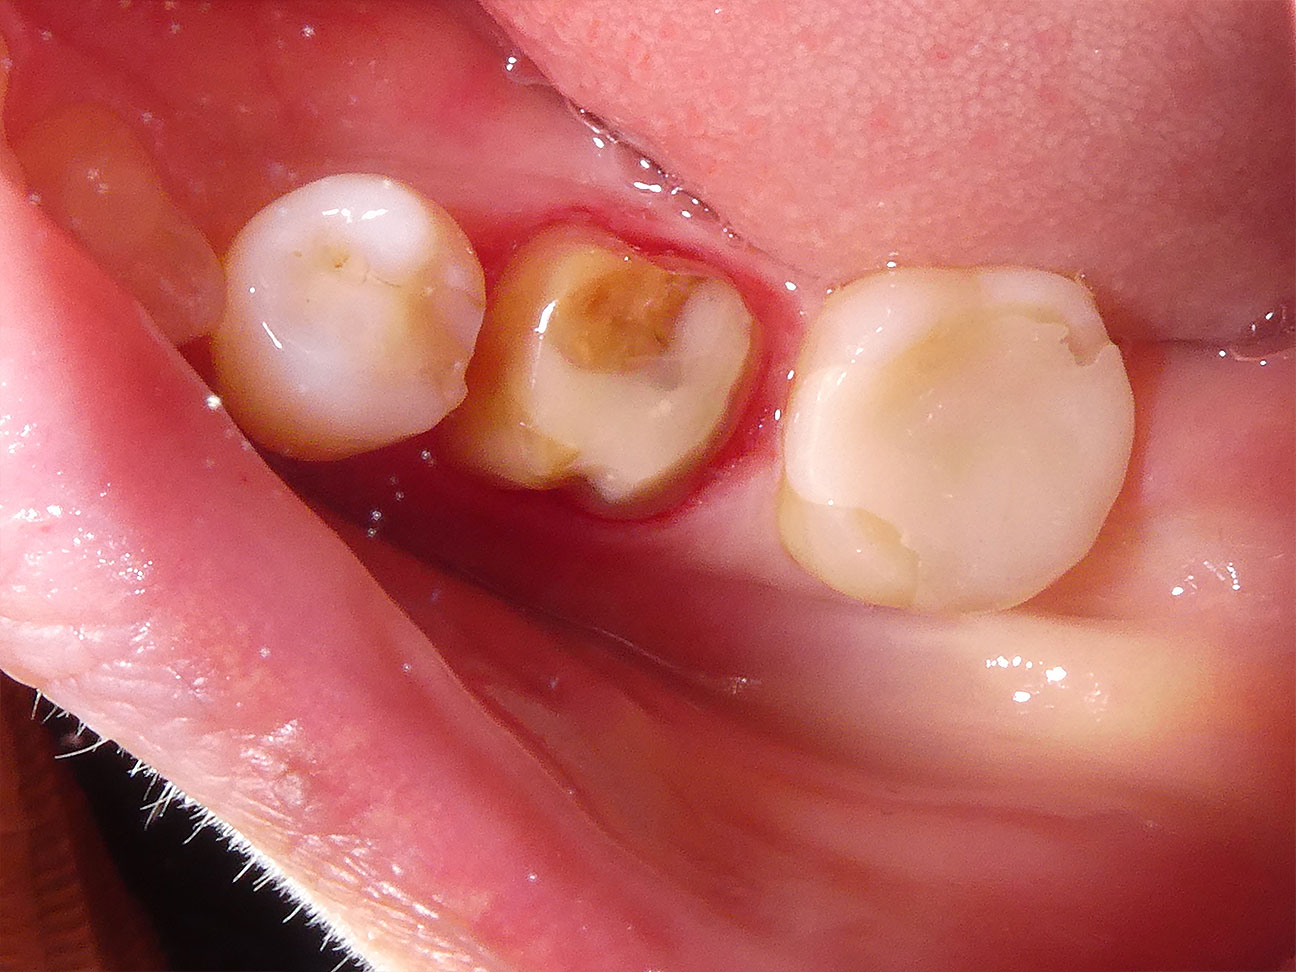

STEP6 形成と圧排

齲蝕検知液を用いて丁寧に時間をかけ虫歯を取ります。その後に被せ物を載せる土台をつくります。そのため歯肉圧排をして印象を採得し、圧排糸を除去した後の写真です。歯と歯茎の隙間がしっかりとでていることが分かると思います。